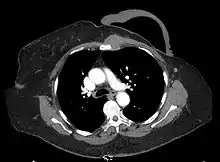

Left internal mammary node recurrence